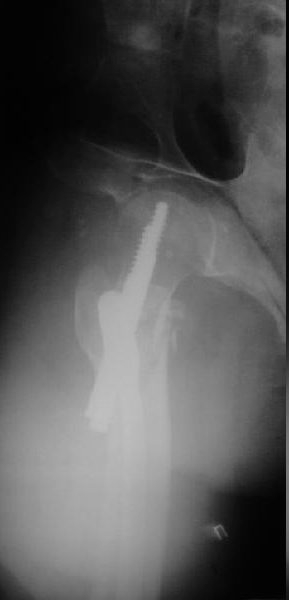

Пациентка, К., 74 лет. В марте 2013 г. упала, диагностирован многооскольчатый чрезподвертельный перелом левой бедренной кости со смещением отломков. 05.03.2013 выполнена закрытая репозиция, остеосинтез левой бедренной кости длинным бедренным гвоздем (ITST, Zimmer) со статическим блокированием отломков. Пациентка в течение 8 недель ходила при помощи ходунков с минимальной нагрузкой на оперированную нижнюю конечность. После выполнения рентгенографии отмечена тенденция к прорезыванию винта и смещение шейки бедренной кости латерально по оси винта (до стержня), нагрузка была ограничена еще на 8 недель. Через 8 недель постепенное градуированное повышение нагрузки до полной. В течение 1,5 месяцев ходила с полной нагрузкой на левую нижнюю конечность, водила автомобиль. Через 1,5 месяца стала отмечать боль в области левого коленного сустава (ранее выполнялось эндопротезирование). Данных за нестабильность компонентов не выявлено. Курсы НПВС по-началу купировали боль в области бедра, через 1 месяц стали малоэффективны. Пациентка наблюдается у невролога в связи с протрузией дисков на уровне пояснично-крестцового отдела позвоночника и периодическими обострениями остеохондороза. С диагностической целью была выполнена блокада бедренного нерва с левой стороны. Боль была полностью купирована, однако возобновилась после прекращения действия анестетика. 10.10.2013 г. пациентка выполнила рентгенографию левого тазобедренного сустава. Выявлен перелом металлофиксатора. Пациентка госпитализирована для лечения.Пациентка до травмы вела активный образ жизни, водила автомобиль. В настоящее время хочет избавиться от болевого синдрома, восстановить опороспособность левой нижней конечности, вернуться к своему обычному ритму жизни.Коллеги три основных вопроса:Какую тактику в данном случае предприняли бы Вы? Варианты удаления металлофиксатора? Чем выполнить реостеосинтез?С уважением, Ершов Дмитрий Сергеевич

Про динамизацию забыли написать. Но проблема из без нее очевидна. Типичная ошибка с "диагональным" положением гвоздя. Т.е. латеральная точка введения и направление к медиальной стенке центрального отломка. Как он должен бы располагаться - зеленая линия на картинке. Соответственно, надо пересинтезировать аналогичным имплантатом, не повторив этой ошибки. Наверно, можно в шейку в передне-заднем направлении ввести 1-2 винта в проекции канала от lag screw.

Все, что было написано по снимку со сломанным гвоздем, остается в силе. Чрезмерно латеральная точка введения, медиальное направление в центральном отломке. То есть варус не устранен, откуда все последующие проблемы. Как решать - уже написал. Конечно, есть и другие варианты реостеосинтеза (клинковая пластина, DHS, даже аппарат) - но тут вполне выполним все еще малоинвазивный реостеосинтез аналогичным гвоздем с исправлением ошибок.

Может я не все понял, создаётся впечатление, что левое бедро синтезировали правым гвоздём.